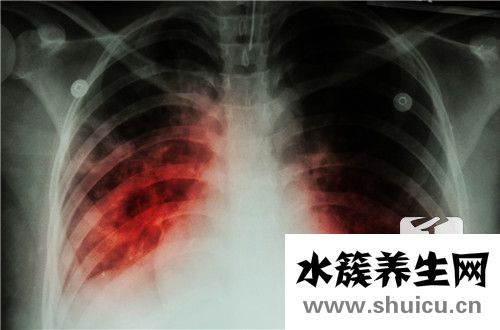

毫無疑問,在發生肺氣腫后,患者人體的各個方面都會受到很大影響。 主要原因是肺是人體核心吸入呼吸系統中的人體器官。 呼吸將受到很大影響。 在治療肺氣腫的整個過程中,除了開處方控制病情發展的藥...